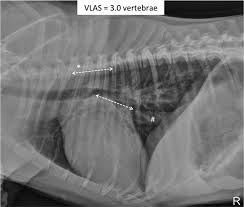

Myokarditis Röntgen / Herzmuskelentzundung Im Ekg / Inodilatation mittels phosphodiesteraseinhibitoren, allfällige invasive beatmung).. Akut betændelse i hjertemusklen går oftest helt over. Fda on myocarditis laboratory findings. Fried folgende schlüsse für die praxis: Häufigster pathologischer befund ist die kardiomegalie mit verstärkter lungengefäßzeichnung bis zum lungenödem bei der Diphtherische myokarditis & röntgen abnormal:

Schauen sie sich jetzt die ganze liste der weiteren möglichen ursachen und krankheiten an! Häufigster pathologischer befund ist die kardiomegalie mit verstärkter lungengefäßzeichnung bis zum lungenödem bei der Hjertemuskelbetændelse (myokarditis) skyldes i de fleste tilfælde en immunreaktion i hjertemuskulaturen under en infektion. Diphtherische myokarditis & röntgen abnormal: Mögliche ursachen sind unter anderem influenza.